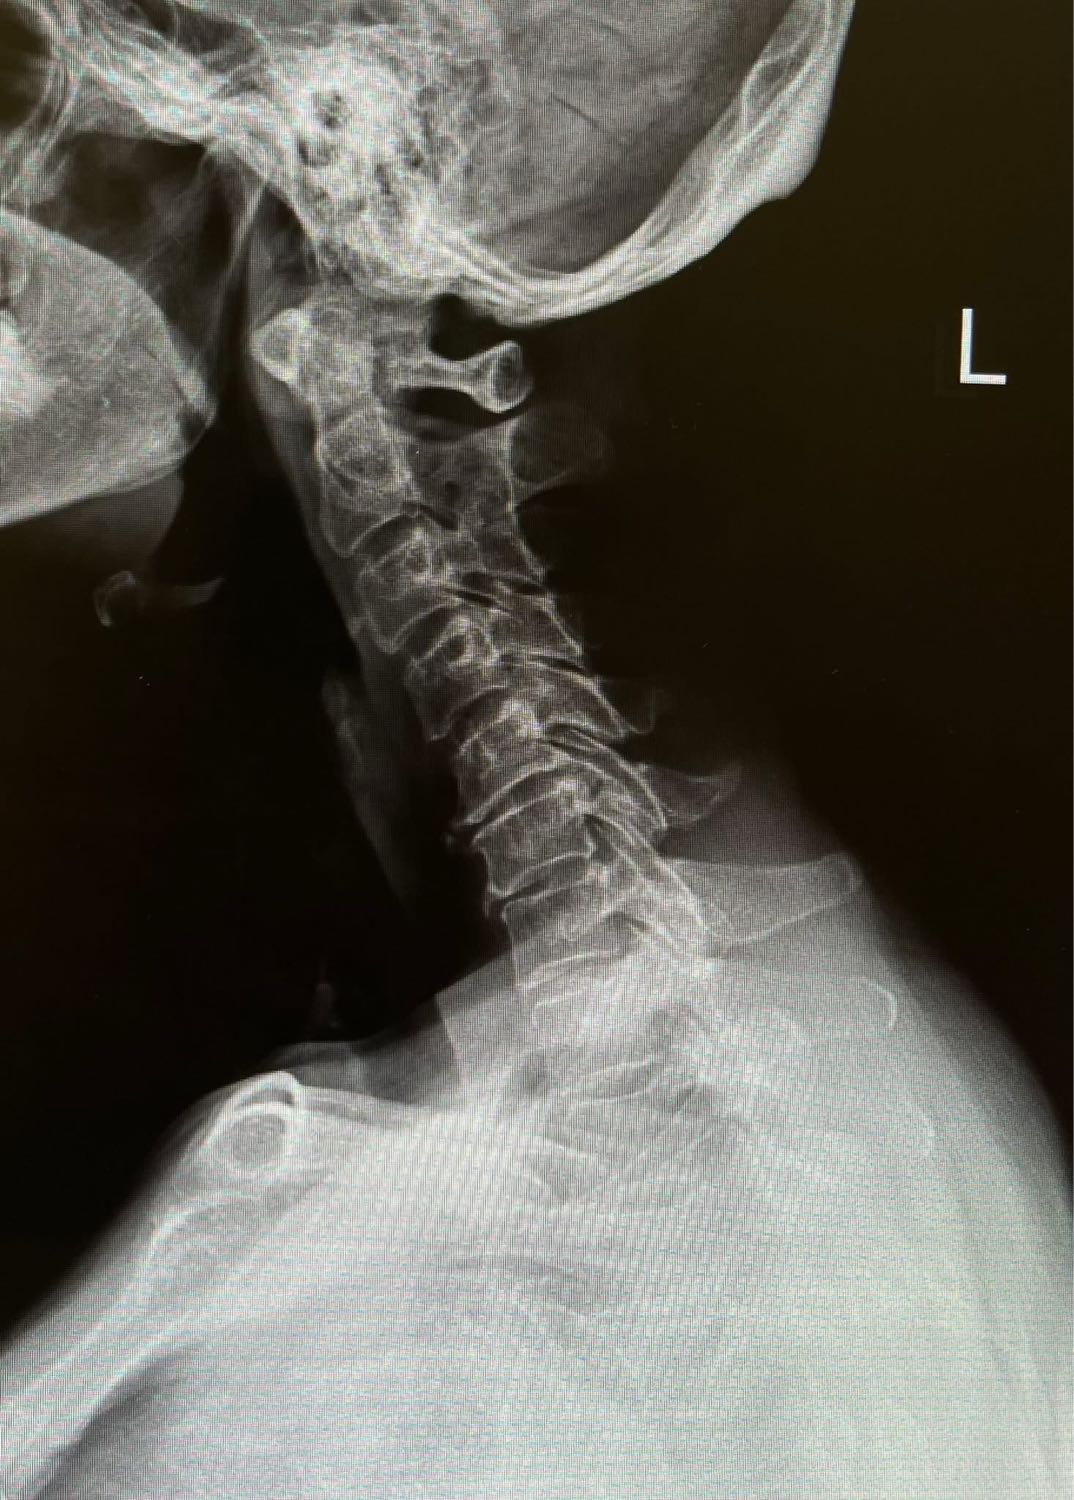

- การตรวจวินิจฉัย (Investigation): หาจำเลยให้เจอ

1. แค่จับๆ คลําๆ บอกไม่ได้ 100% ครับ ต้องใช้เทคโนโลยีช่วย:

### เอ็มอาร์ไอ (MRI): พระเอกตัวจริง การทำ MRI จะทำให้เห็น "เนื้อเยื่ออ่อน" อย่างเส้นประสาทและหมอนรองกระดูกได้ชัดเจนมาก หมอจะชี้ได้เลยว่า "ปลิ้นตรงข้อที่ 5 กดทับเส้นประสาทข้างซ้าย" เป็นต้น